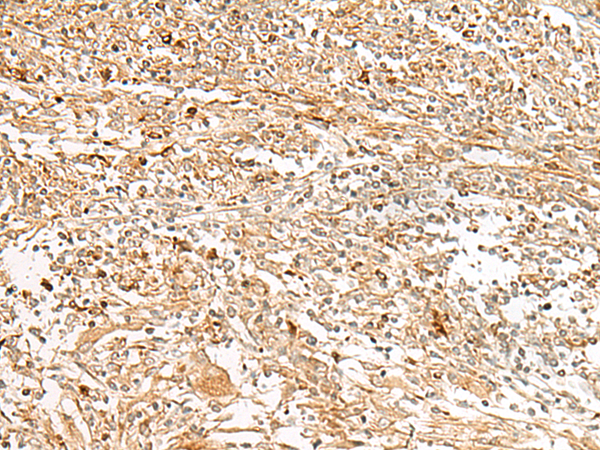

分类: 科研抗体货号: P13460别名: LGP1; D11LGP1应用: IHC反应种属: Human